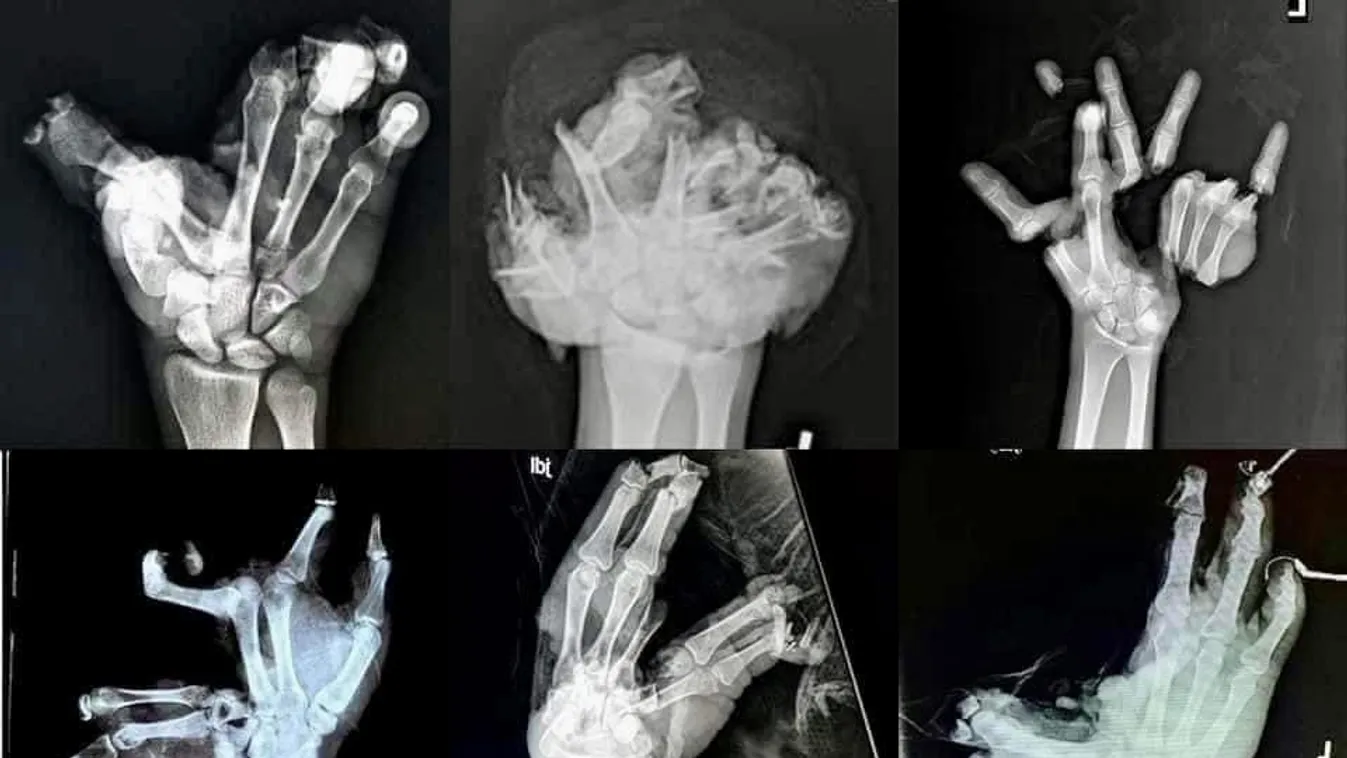

Az Országos Mentőszolgálat a közösségi oldalán tett közzé egy elborzasztó posztot arról, milyen súlyos következményekkel járhat a petárdázás. A nap folyamán a Készenléti Rendőrség Tűzszerész Főosztályának vezetője is arra figyelmeztetett, hogy ez a fajta tevékenység akár csonkolásos sérülést is okozhat.